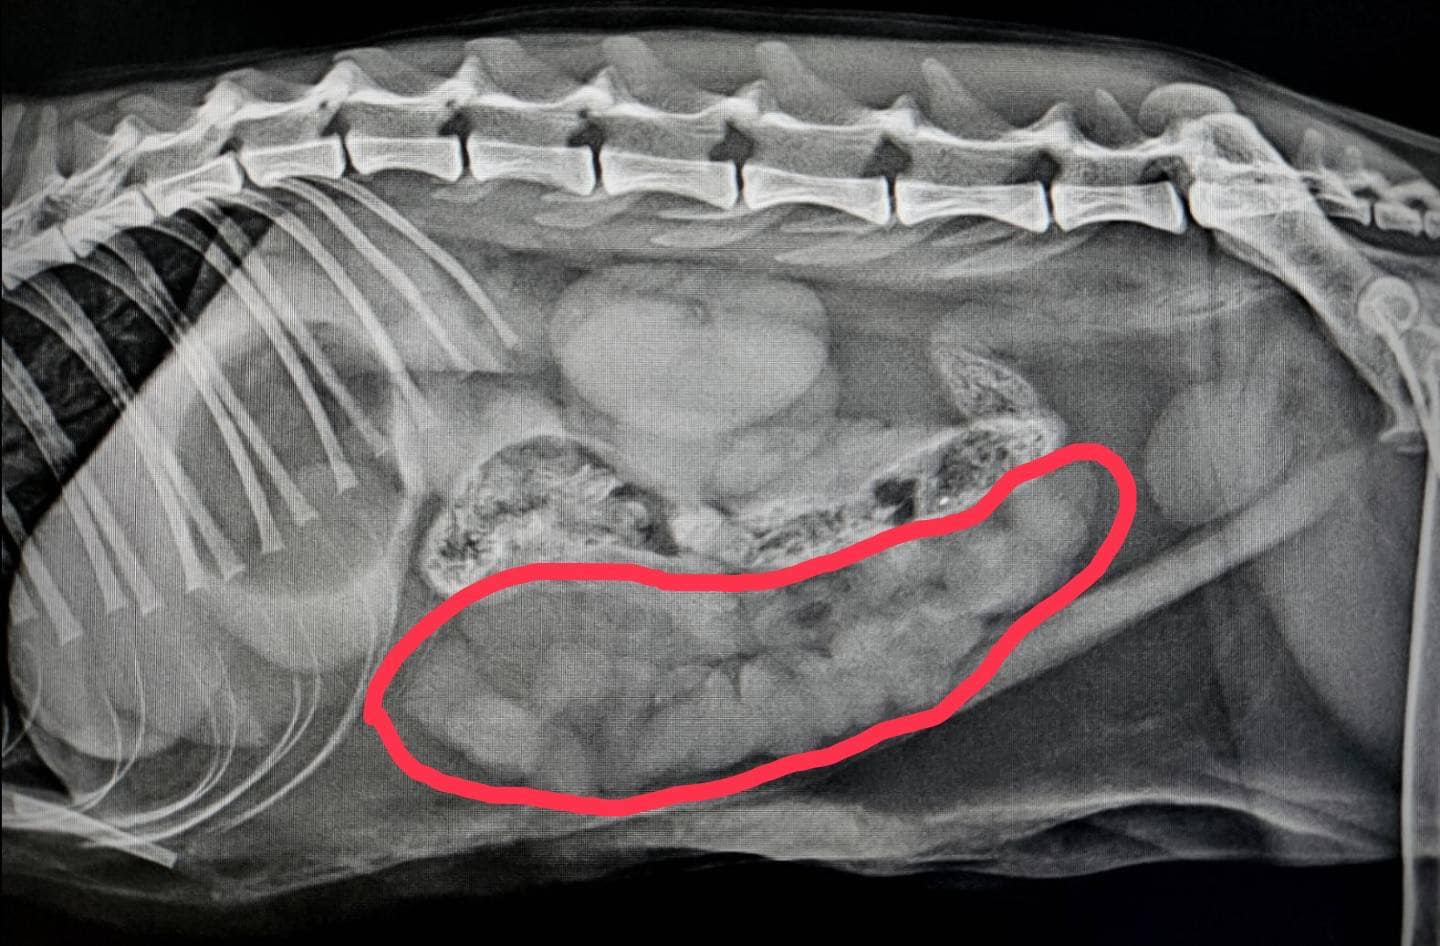

線性異物

4天不吃飯的NANA

無精打采還不停嘔吐

發現舌下纏著線

#X光檢查

腸道被線勒住,呈手風琴影像

#腸道線性異物 #緊急手術 #住院治療

將卡在胃腸道內的線取出